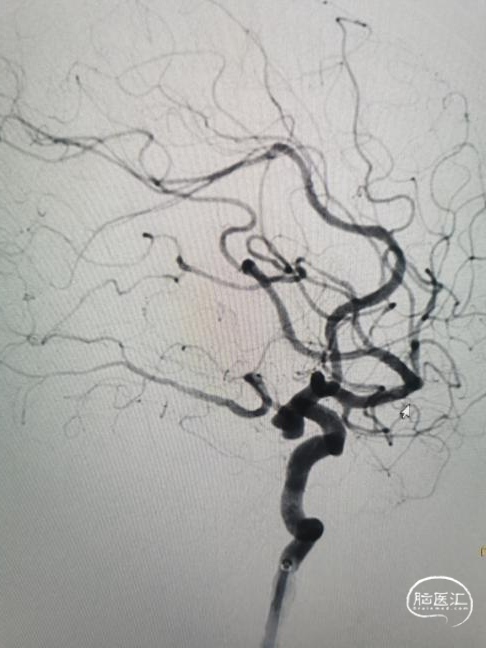

DSA:右侧颈内动脉交通段见一动脉瘤,瘤颈约4.3mm,瘤体大小约7.9mm*6.9mm,后交通动脉自瘤体发出,左侧颈总造影未见明显异常。左侧椎动脉造影基底动脉及其后显影不良,右椎造影,压颈后造影,大脑后动脉显影良好,可见造影剂返流至动脉瘤瘤体内。

术前造影显示右侧颈内动脉后交通动脉瘤。

工作位造影